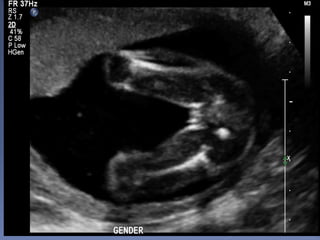

When

 The earliest time is 12 weeks if in right

position

 Best done between 17-20 weeks

gestation

 What you will see????

 Male: penis or scrotum

 Female: The 3-lines sign which denotes

the labia

 The absence of the penis must not be

taken as sufficient evidence of the fetus

being a girl

AGAIN

MALE:dome shaped genital swelling with a

cephalic-directed phallus

FEMALE:three or four parallel

lines representing the labia